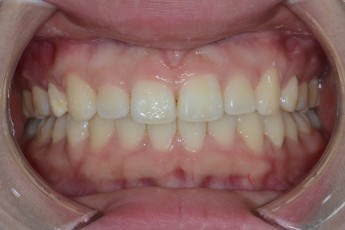

Before

After